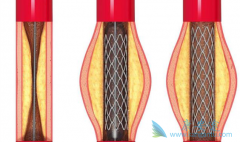

什么是 心脏支架手术 ?可以把心脏支架想象成是个细长的金属笼子,放在血管里就可以把即将堵死的血管撑开,心脏支架非常的细小,直径大约在2~4毫米,长几厘米,有空心、圆柱、网状金属管,一般都是用钛合金制成,是世界上最昂贵的一种金属。 心脏支 ...

不少人都听过心脏支架手术,这种手术堪称是当代心脏病学最伟大的一项发明。你知道这个小小的支架是怎么放到心脏里去的吗? 心脏支架 是通过介入手术的方式植入到人体的,我们可以从心脏介入手术可是说起,这样更好理解。心脏介入原理其实并不复杂。 ...

为了改善冠心病介入治疗短期和长期的疗效与安全性,所以研发了支架。第一代支架是金属裸支架,使冠心病介入治疗前进了一大步,使介入治疗变得非常安全,当血管发生严重狭窄时单纯球囊扩张预处理后,再用支架把血管完全撑开,就能解除心肌缺血危险,而且 ...

心脏支架 选哪种?放最好的支架?还是放最贵的支架?今天就给大家答疑解惑!心脏支架由具有强支撑力的合金制成,不同厂家支架的金属结构略有差别。心脏支架没有植入体内之前,包裹在球囊外面。植入时给球囊加压,支架打开至预定直径,使支架与血管壁完 ...